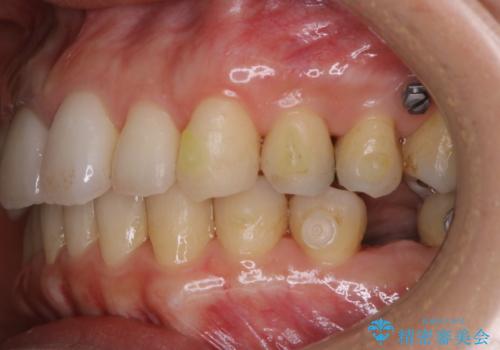

- インビザラインでのマウスピース矯正中にステインや着色を取りたいとのことでした。

PMTC60分コースを行いました。

PMTC(保険外治療)は、毎日の歯磨きで落としきれない汚れや、コーヒ、紅茶・タバコのヤニなどの着色も除去します。目には見えない歯と歯の間・歯肉の境目・インビザライン中はアタッチメント周囲などに残っているプラーク(歯垢)もしっかり取り除きます。PMTCでは専門的な機械や材料を使用して、徹底的に汚れを除去するため、虫歯・歯周病・口臭予防などにつながります。